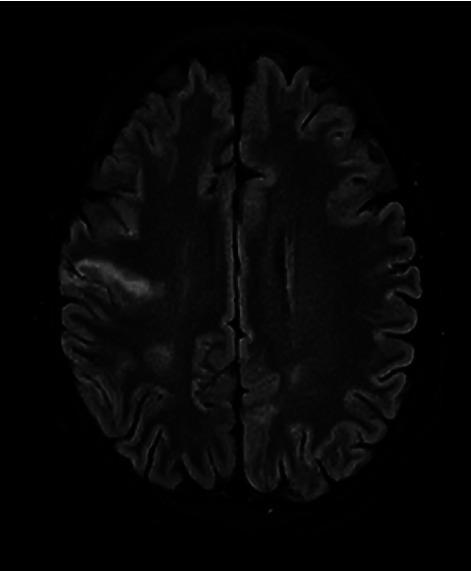

Cerebritis and infective endocarditis caused by are very rare. A 56-year-old man presented with slurring of speech and generalized body weakness of 1 week duration. He did not have any past medical history. On systemic examination, he had mild slurring of speech and facial asymmetry and was initially treated for multifocal chronic cerebral infarcts. was isolated from blood culture on day 5 of admission. A diagnosis of neurolisteriosis was made as contrast-enhanced-computed tomography (CECT) of the brain showed right frontal cerebritis. He was treated with intravenous benzyl penicillin. His general condition was improving until day 13 of hospitalization whereby he developed haemoptysis and severe Type 1 respiratory failure requiring reintubation. An urgent transthoracic echocardiogram revealed a large vegetation at the anterior mitral valve leaflet measuring 2.01 cm. No active arterial bleeding was seen on computed tomography angiography (CTA) of the thorax. Magnetic resonance imaging (MRI) of the brain showed evidence of right frontal cerebritis. He continued to deteriorate and succumbed to his illness after 3 weeks of hospitalization. Clinicians should be aware of such an occurrence and prompt recognition and adequate treatment are necessary in cases of cerebritis and infective endocarditis as both are deadly entities.

由[病原体未提及]引起的脑脊髓炎和感染性心内膜炎非常罕见。一名56岁男性出现言语不清和全身乏力,持续1周。他既往无任何病史。全身检查时,他有轻度言语不清和面部不对称,最初被诊断为多灶性慢性脑梗死并接受治疗。入院第5天血培养分离出[病原体未提及]。脑部增强计算机断层扫描(CECT)显示右额叶脑脊髓炎,从而诊断为神经李斯特菌病。他接受了静脉注射苄星青霉素治疗。直到住院第13天,他的一般状况一直在改善,然而此时他出现咯血和严重的1型呼吸衰竭,需要重新插管。紧急经胸超声心动图显示二尖瓣前叶有一个2.01厘米的大赘生物。胸部计算机断层血管造影(CTA)未发现活动性动脉出血。脑部磁共振成像(MRI)显示右额叶脑脊髓炎的迹象。他的病情继续恶化,住院3周后死亡。临床医生应意识到这种情况的发生,对于脑脊髓炎和感染性心内膜炎病例,及时识别和充分治疗是必要的,因为这两种情况都是致命的。